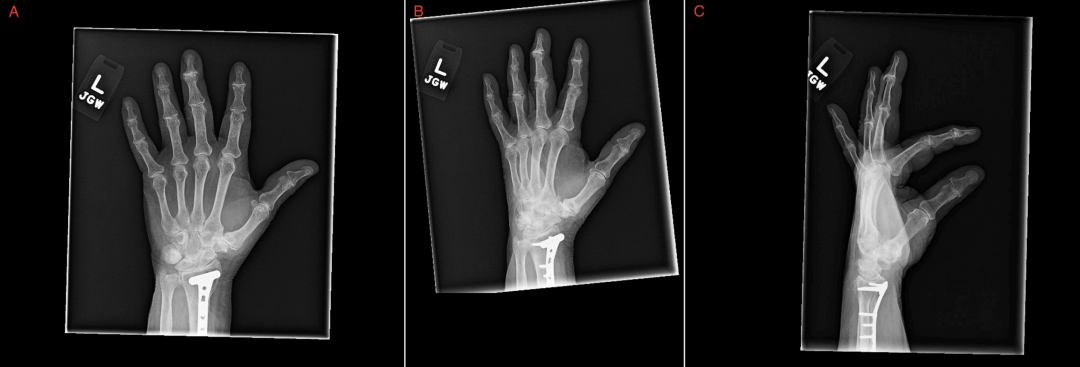

影像学检查:右侧肱骨、前臂增强CT(图1-图3)及左手X线摄片(图4)未见急性结构性或血管性病变;左手广泛存在退行性改变。

图4 左手多视图 X 线片,显示广泛慢性退行性改变

此外,患者高龄、肥胖及已存在的OA病史可能掩盖炎症性病变的表现,临床中两种疾病常合并存在,容易导致漏诊或延误。因此,面对不典型关节症状时,临床医生应保持警惕,综合临床表现、血清学与影像学结果进行全面评估,避免因单一指标阴性或存在退行性病变病史而忽视RA的可能性。